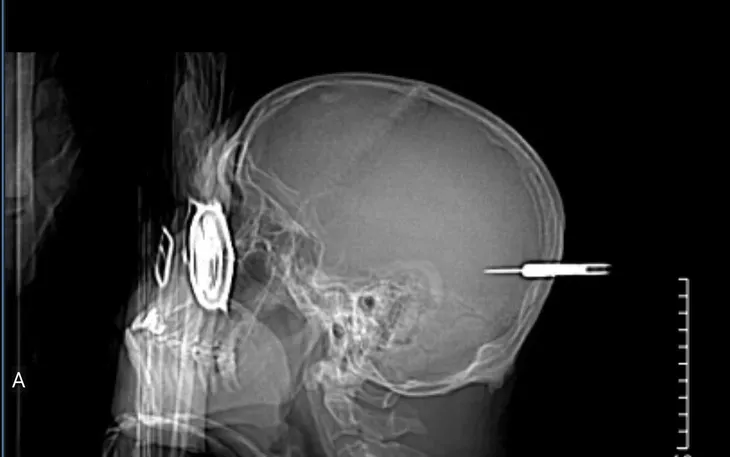

Bệnh nhân nam, 66 tuổi, bị một mũi phi tiêu ném trúng vùng đầu khi đang tham gia hoạt động vui chơi. Người bệnh nhập viện trong tình trạng chấn thương sọ não và đã được cấp cứu khẩn cấp để lấy dị vật.